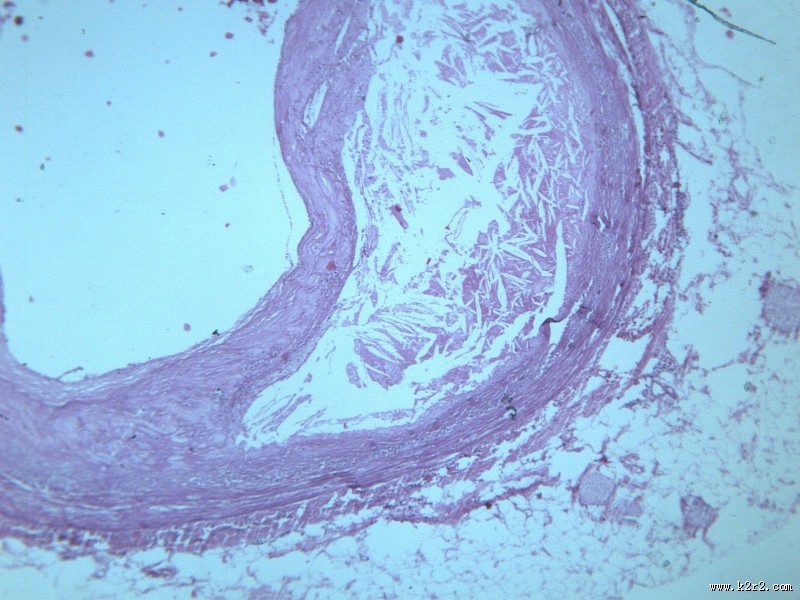

首页 > 其他类别 > 动脉粥样硬化(12张) > 动脉粥样硬化 第3张

动脉粥样硬化 - 第3张